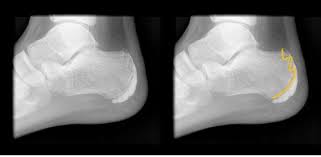

족저근막은 발바닥의 아치 모양 곡선을 유지하고 발에 전해지는 충격을 흡수하는 스펀지 같은 역할로 발바닥 근육을 감싸고 있는 얇은 막입니다. 이곳에 지속적인 충격, 마찰이 전달되면 결국 염증이 생겨 살살 걸어도 발이 아프게 됩니다.

물리적인 자극이 지속될수록 발뒤꿈치뿐 아니라 발 안쪽까지 아프고 쑤시는 증상을 보이기 때문에 가급적 빨리 치료할수록 경과도 좋은 편입니다.

혹시 내가 족저근막에 이상이 있는지 알아보려면 자고 일어난 뒤 제일 처음 발을 디뎌 보면 됩니다.

수면 중 발이 바닥에 처진 상태에서 족저근막이 수축되었다가 다시 걷기 시작하면 체중이 부하되면서 자극을 받습니다.

첫 발을 내디딜 때 가장 심한 통증이 생기고, 발가락을 발 등 쪽으로 당겼을 때도 확인해 보세요.